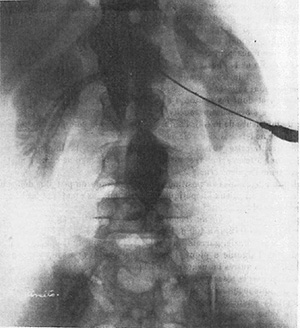

図1. 盲目的直接穿刺による経腰的腹部大動脈造影

【解説】 Dos Santosの直接穿刺による経腰的大動脈造影(translumbar aortography)に関する論文は,これを予告した1929年1月の初報[1],完成を報告した同年3月[2]のものがあり,いずれもポルトガル語で書かれている.本稿はこれとほぼ同時にフランス外科学会で行なった講演の記録が,同学会誌4月にフランス語で掲載されたもので,内容的には両者を含み,供覧されている写真は第2報とほぼ同じである.

前半は四肢動脈,広範は腹部大動脈造影について,それぞれ穿刺,造影,撮影に分けて手技を詳述している.造影剤はヨウ化ナトリウムで,四肢では25%,大動脈は100%を使用している.大動脈造影については,背臥位で傍脊柱を盲目的に穿刺する方法であるが,これは内臓神経ブロックと同じ方法であり,高濃度造影剤の使用も含めて安全性に問題はないとしている.提示されている写真はそれなりにきれいなもので(図1),症例3ではたまたま腹腔動脈が穿刺されており,はからずも史上初の選択的腹腔動脈造影となっている.